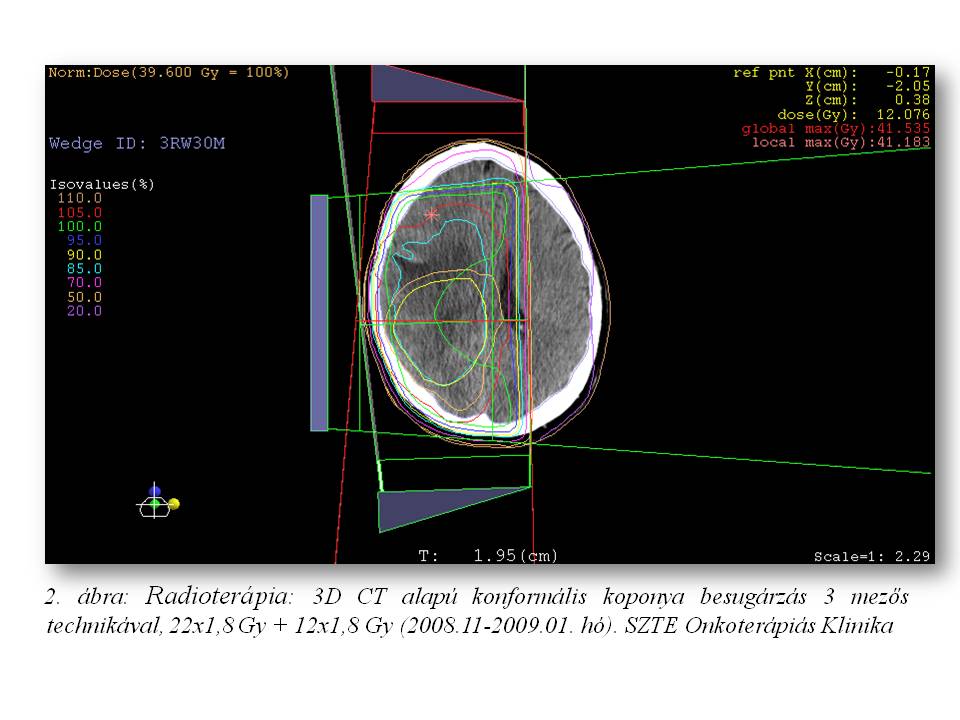

A 39 éves férfi betegnél 2004 nyarán jobb oldali parieto-occipitalis térfoglaló folyamatot detektáltak CT vizsgálattal, mely 2008 augusztusában növekedni kezdett (1. ábra). Az elvégzett biopszia grade II oligodendrogliomát igazolt. A beteg ezt követően definitív dózisú (22x1,8 Gy + 12x1,8 Gy) irradiációban részesült (2. ábra). 2 éven át fokozatos tumor regressziót, és stabil betegséget észleltünk, majd klinikailag stabil állapota mellett készült MR képalkotás 2010 júniusában tumor progressziót mutatott (3. ábra). Ekkor funkcionális MR és diffúzió súlyozott tractographia alapján neuronavigációs éber műtét során a makroszkópos tumor eltávolítása megtörtént. A hisztopatológia ekkor anaplasticus irányba transzformálódó, grade II-III oligodendrogliomát írt le. Posztoperatív 20x1,6 Gy dózisú reirradiáció történt, majd temozolomide monoterápia indult, mely 23 cikluson keresztül folytatódott (4. ábra). Ismételt tumor progresszió miatt 2012 szeptemberében betegünk reoperáción esett át, recidiváló, grade III-IV malignusan transzformálódó oligodendroglioma diagnózisával. A mozgásrehabilitáció mellett bevacizumab monoterápia indult egyedi méltányossággal, melyet 2013 júliusában kontroll MR által leírt subacut bevérzés miatt 4 ciklust követően a beteg kérésére felfüggesztettünk (5. ábra), 10 hónap viszonylagos jó állapot után gyors progresszió, majd 2014.06.27-én exitus következett be.